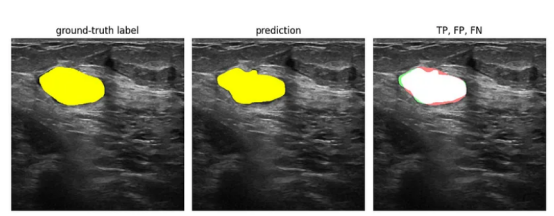

在模型进行非零预测但标签中的像素为零的情况下,这些像素为假阳性(FP)。如果标签中的像素为非零,但模型的预测为零,则这些是假阴性(FN)。下面是一个例子:

真阳性、假阳性、假阴性(图像来源:乳腺超声图像数据集)

其中,左边的矩形中显示的是标签。中间矩形中给出的是模型的预测结果。在右边的矩形中,我们用白色标记了真阳性(TP):预测像素与标签像素匹配。假阳性(FP)是标签中为零的非零预测像素,并标记为绿色。假阴性(FN)是标签中存在非零像素的零值预测像素,并且被标记为红色。